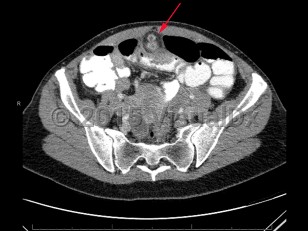

A Meckel diverticulum is a remnant of the omphalomesenteric duct in the distal ileum. Patients with a Meckel diverticulum typically present with painless hematochezia and/or bowel obstruction. Alternatively, a Meckel diverticulum should be considered if an abdominal mass is detected or in cases of abdominal pain, often right lower quadrant, of unclear etiology.

A Meckel diverticulum can predispose patients to intussusception, ulcer formation, bowel inflammation, perforation, or foreign body entrapment, all occurring at the diverticulum.